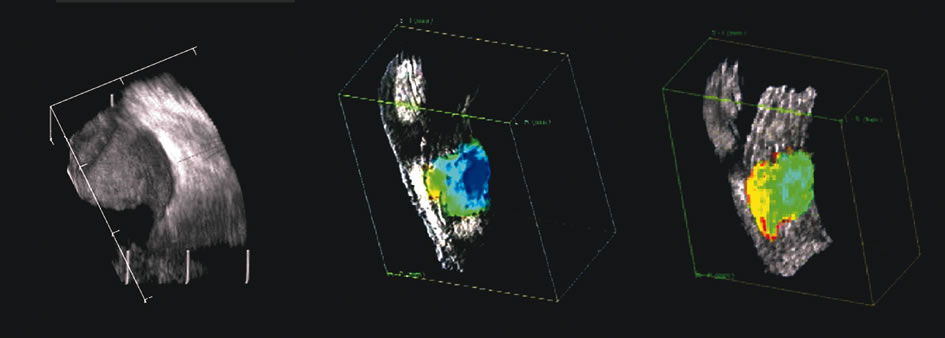

The representation of volume and three-dimensional perspectives of the diseased vitreous, retinal detachment, choroidal detachment, and tumors can add to presurgical conceptualization and is critical to characterization of tumors in relation to prediction of lethality.45 In addition, volume measurement of the choroid permits studies of both surgical and physiologic rates of clearance of hemorrhage, whereas vitreous volume studies can make the estimation of gas or other vitreous substitutes for replacement more accurate (Fig. 25).

Fig. 25. A 3D reconstruction of serial scans of a posterior pole melanoma taken with a 10 MHz transducer (left) shows the extent and relative asymmetry of the tumor within the vitreous cavity. 3D biometry can be useful for treatment planning for radiotherapy and brachytherapy. 3D reconstructions of 50 MHz serial ultrasound scans and parameter images of a melanoma involving the ciliary body and anterior uvea (center, right) before and after treatment with combined ultrasound hyperthermia and brachytherapy. Changes in the concentration of ultrasound scattering elements related to tissue necrosis are seen as color scale in the pre- and postimage region of the tumor shifts, from blue, indicating relatively low acoustic concentration, to yellow and green, indicating higher concentrations of scatterers.